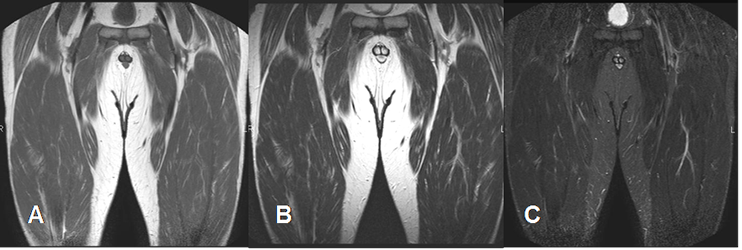

En la RM la señal de intensidad (SI) del músculo normal es un poco mas hiperintensa que el agua e hipointensa en relación a la grasa en T1 e hipointensa al agua y la grasa en T2. (5). En STIR la SI es hipointensa en relación con el agua y la grasa. (6). (Fig 4).

Fig 4. Señal normal del músculo.

A: RM coronal en T1. Músculo algo hiperintenso en relación al agua e hipointenso, con la grasa.

B: RM coronal en T2. Músculo hipointenso en relación con el agua y la grasa.

C: RM coronal en STIR. Músculo hipointenso en relación al agua y la grasa.